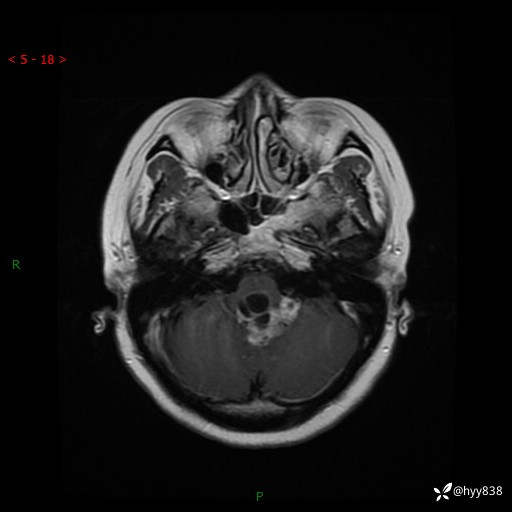

病例中年女性,头晕1年余。看看什么是软,什么是见缝钻---结果公布~

性别:女

年龄:47岁

简要病史:头晕1年余,间断恶心不伴呕吐

颅脑MRI平扫+DWI

轴内、轴外占位

轴内或轴外肿瘤